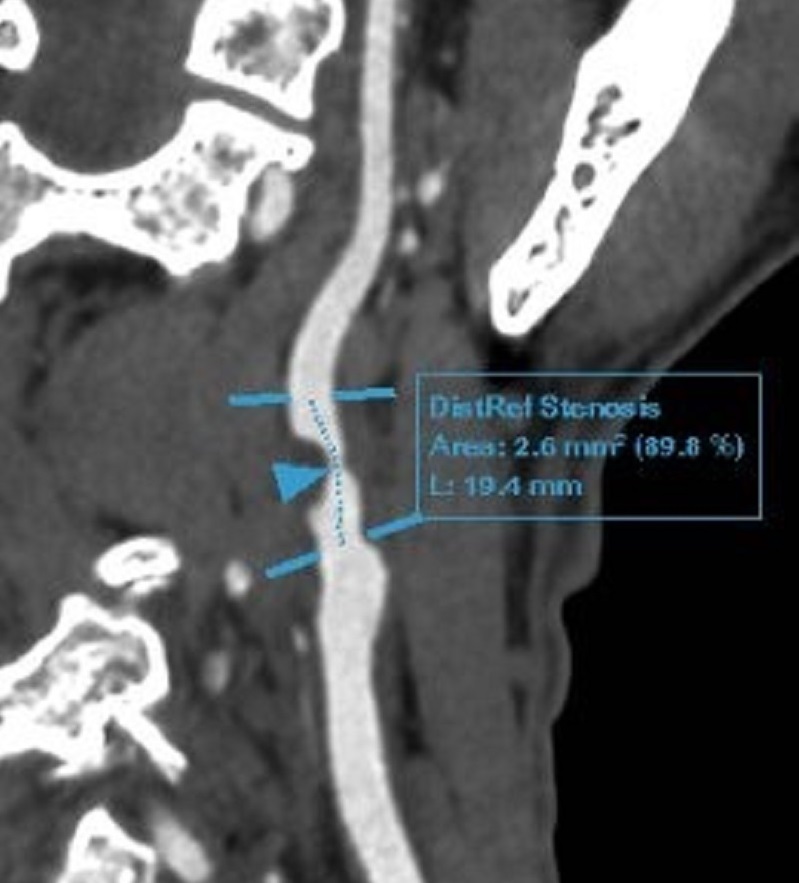

Ông Đ được bác sĩ chỉ định thực hiện xét nghiệm và các kỹ thuật chẩn đoán hình ảnh chuyên sâu tìm nguyên nhân gây đau đầu. Sau đó, ông được chẩn đoán mắc bệnh động mạch cảnh do xơ vữa, hẹp nặng 90% động mạch cảnh trong bên phải, lóc tách nhỏ gốc động mạch cảnh trong bên trái. Bệnh động mạch vành mạn tính. Rối loạn lipid máu.

“Trường hợp của ông Đ đã hút thuốc lá gần 30 năm (tương đương hơn 6.000 bao), đi khám vì các cơn đau đầu nhẹ thoáng qua nhưng đã phát hiện mảng xơ vữa gây hẹp 90% gốc động mạch trong phải, lóc tách nhỏ gốc động mạch cảnh trong. Đây là minh chứng rõ ràng cho tác động nghiêm trọng và âm thầm của thuốc lá lên hệ mạch máu não và tim mạch. Bên cạnh đó, khi thấy các dấu hiệu không rõ ràng như: Chóng mặt, buồn nôn, yếu liệt tay chân hay rối loạn ý thức, người bệnh vẫn tiềm ẩn nguy cơ cao bị đột quỵ nếu không được phát hiện và can thiệp kịp thời”, BS Nam nhấn mạnh.